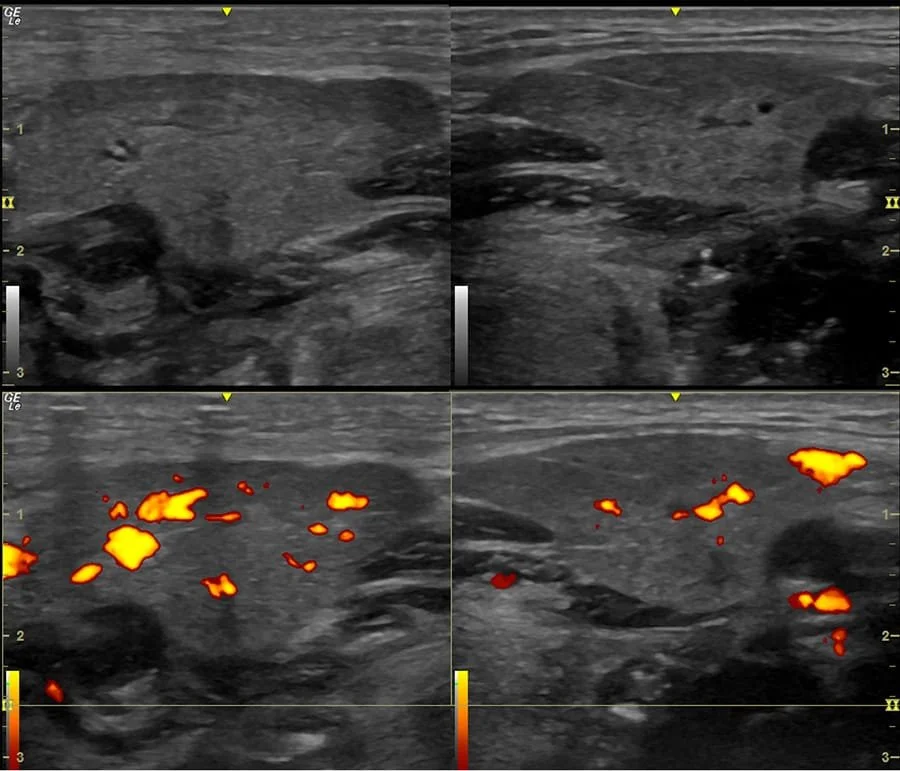

Ultrasonido de una Glándula Parotida

¿Para qué sirve la ecografía en el diagnóstico de Sjögren?

La ecografía es un examen que permite ver por dentro las glándulas salivales (como las parótidas y las submandibulares) sin dolor y sin radiación.

En el síndrome de Sjögren, estas glándulas pueden inflamarse o cambiar su estructura, y la ecografía ayuda a detectar esos cambios.

Con este estudio se puede:

• Identificar si las glándulas están inflamadas o dañadas por el sistema inmune.

• Ver si tienen un aspecto irregular, algo típico en las personas con Sjögren.

• Distinguir si los síntomas (boca seca, inflamación o dolor) se deben realmente a Sjögren u otra causa.

• Ayudar al reumatólogo a confirmar o descartar el diagnóstico sin necesidad de estudios más invasivos en muchos casos.